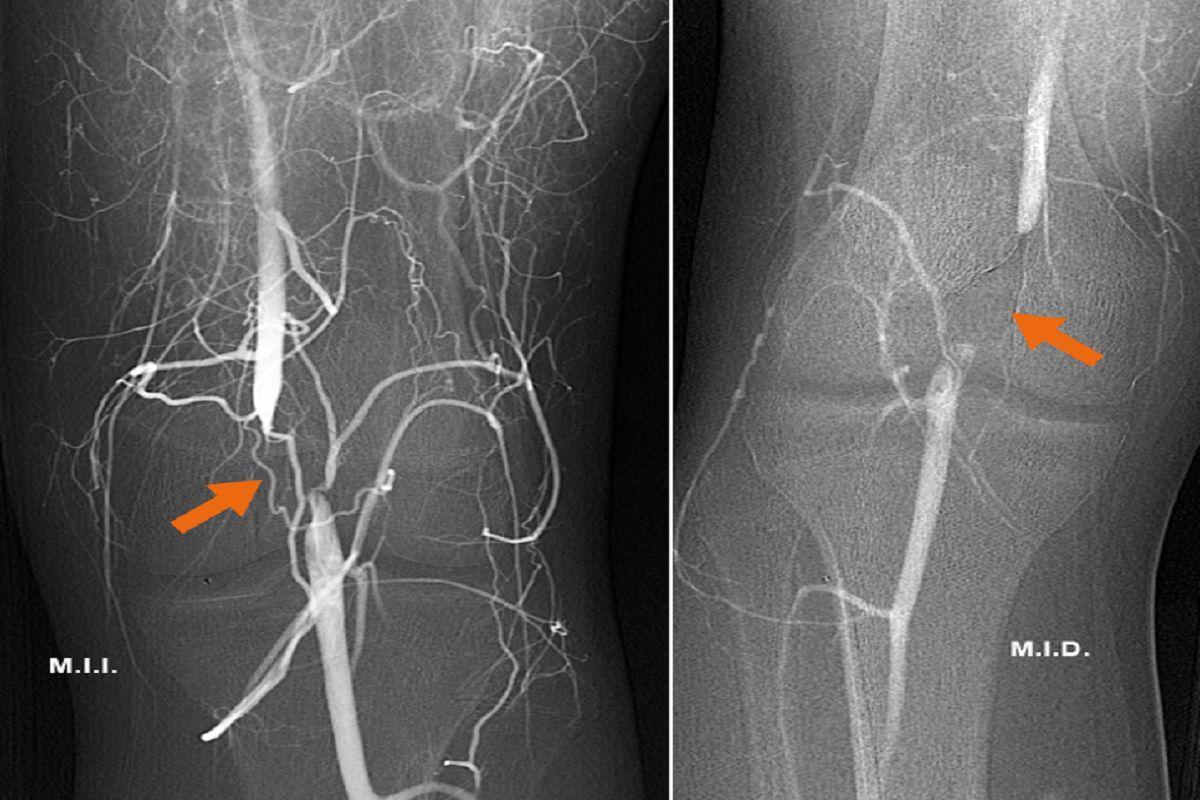

Tal y como indica el doctor Santiago Zubicoa, responsable de la Unidad de Radiología Vascular Intervencionista del Hospital Ruber Internacional, el diagnóstico precoz del Síndrome de Atrapamiento de la Arteria Poplítea (SAAP) se realiza mediante un eco-doppler dinámico de miembros inferiores.

Una técnica no invasiva que permite medir el flujo sanguíneo utilizando ultrasonidos.

Posteriormente, el diagnóstico se confirmará con una arteriografía dinámica también de ambas extremidades inferiores.

"Una vez realizadas las pruebas de imagen que nos confirmen el diagnóstico de SAAP debemos programar el tratamiento quirúrgico", matiza Zubicoa.